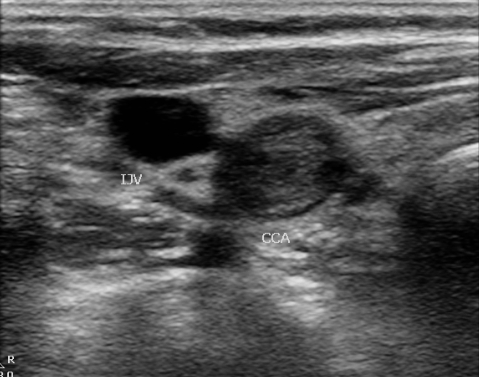

The diagnosis of carotid artery occlusion is made by vascular imaging. Duplex ultrasound can show absence of flow. The duplex can show thrombus in the artery and absence of flow with pulse wave and color Doppler. A clue to the diagnosis is the waveform in the common carotid artery. It becomes more high resistance than usual: